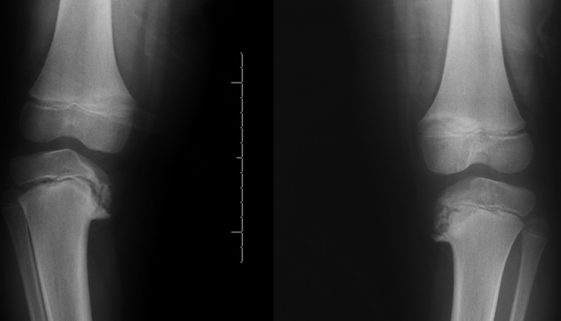

O que é?É uma doença que afeta a fise de crescimento da face interna do joelho, promovendo uma deformidade conhecida como geno varo – ou seja, o joelho se afasta para fora, ficando arqueado, como na posição para cavalgar.É dividida em dois tipos: Blount da infância e Blount do adolescente. Vamos falar aqui predominantemente do Blount […]